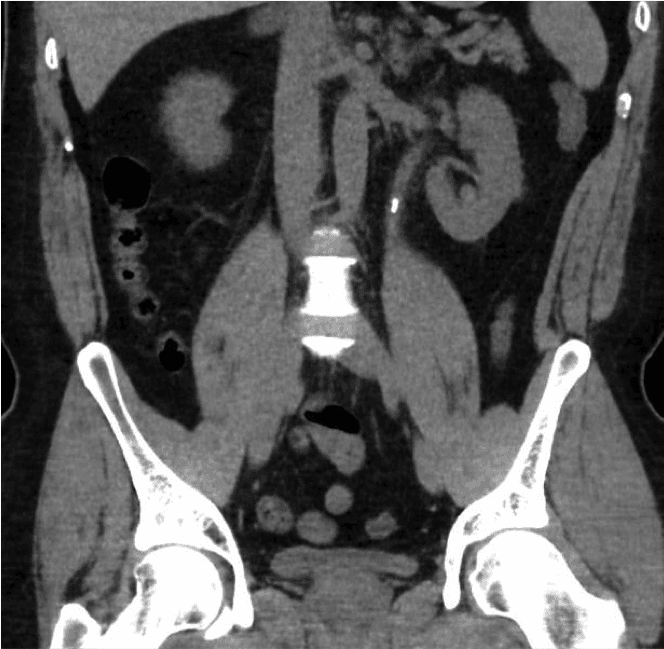

La litiasis renal es una de las enfermedades más comunes en la era moderna. Su prevalencia varía considerablemente según la ubicación geográfica, oscilando entre el 8 % y el 19 % en hombres y entre el 3 % y el 5 % en mujeres en países occidentales [1,2]. El número de hospitalizaciones por litiasis renal en el Reino Unido aumentó un 63 %, alcanzando las 83 050, entre 2000 y 2010 [3]. La creciente prevalencia de la litiasis renal supone una importante carga económica y clínica para nuestro sistema sanitario.Los cálculos renales pueden aparecer incidentalmente en una exploración realizada por otros motivos o presentarse con síntomas como dolor, infección urinaria o hematuria (sangre en la orina).